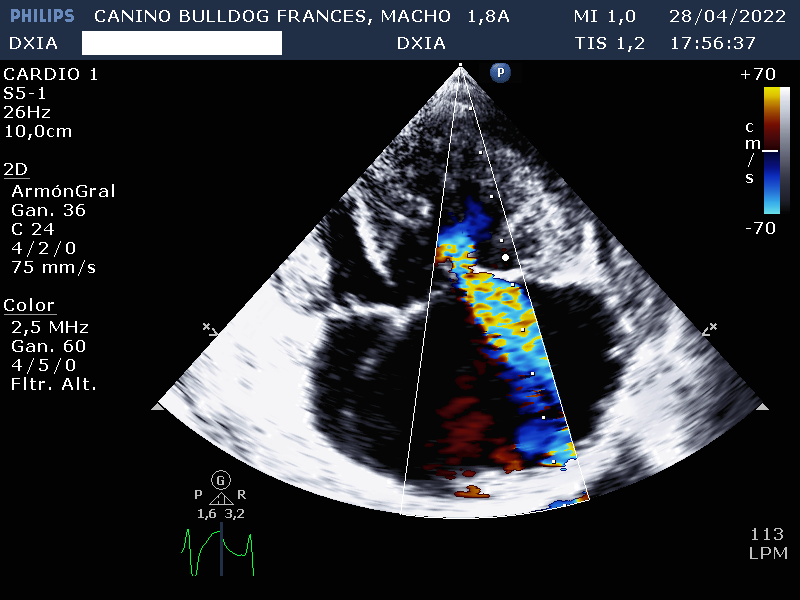

- Valvúla pulmonar: normoimplantada. Engrosamiento valvular con separación incompleta de las comisuras y dilatación post estenótica del tronco pulmonar. Gradiente de presión compatible con estenosis pulmonar severa. Movimiento paradójico del septo interventricular.

- Válvula tricúspide: Displasia de sus valvas con dilatación severá de AD. Marcado aumento e hipertrofia concéntrica de las paredes del ventrículo derecho.

- No cambios compatibles con existencia de HP.

Por lo tanto el estudio ecocardiográfico es compatible con posible soplo de grado IV en el lado de derecho y displasia de la válvula tricúspide con dilatación severa de AD y VD. Además, presenta estenosis pulmonar severa con leve hipertrofia de la pared del VD.